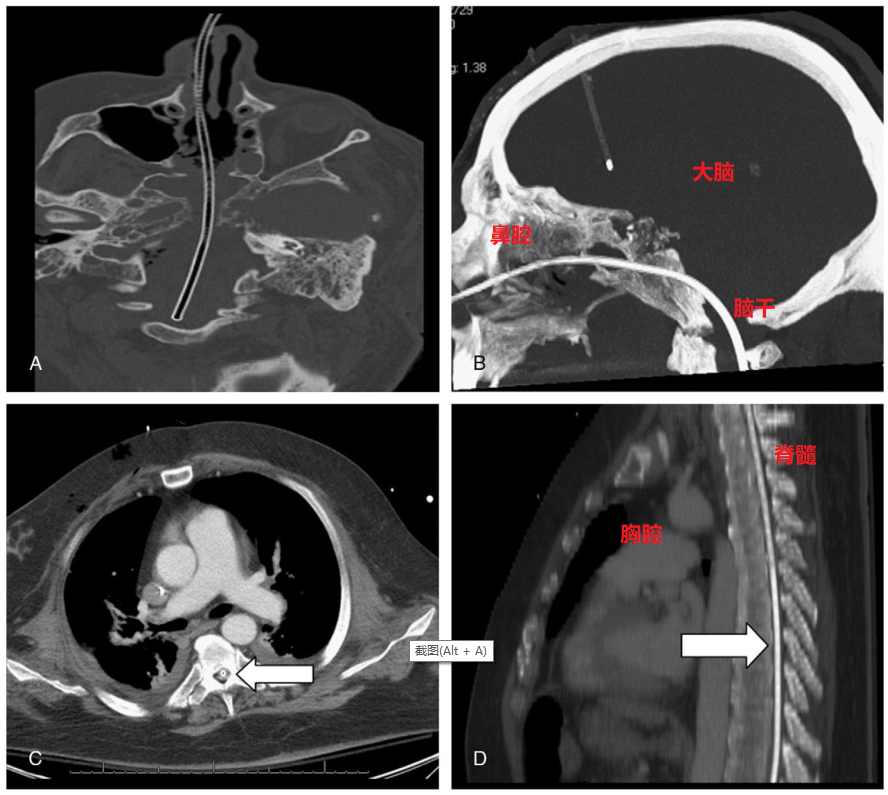

第二天做头颅CT(做头颅CT原因不明,可能是为了明确大脑情况),发现胃管已经插到了颅内。下列是病人家属贴出来的当时CT报告:

头颅CT所见:鞍区肿瘤术后改变,颅底局部骨质缺如,经鼻可见一管腔经鞍底进入颅内,盘曲于脑室周围,头端位于右侧枕叶,周围见放射状金属伪影,脑室扩张,积血/液/气。

从这张CT报告来看,确定胃管是插入大脑内无疑了。

由于鼻腔顶部那块很薄的颅骨有了破损(手术时切开的),并且可能还没愈合,这时候插胃管,尤其是含有导丝的比较坚韧鼻空肠管是完全有可能不小心捅破这个骨质伤口,进入大脑的,就好像这样:

所以,对于颅底骨折、颅底手术后的病人来说,胃管是真的有可能进入大脑的,这种并发症罕见,但并非不可能。因为鼻腔和大脑真的只有一骨之隔,而且这块骨质是很薄的。

曾经就有病例报道CT:鼻胃管从鼻腔进入,穿破了颅底骨质(病人也是中枢神经肿瘤,做了手术,颅底存在骨质缺损),这根胃管是含有导丝的,

比较坚韧,穿破颅底骨质后,进入大脑、穿过脑干,竟然随着脊髓一路往下走,经过病人颈段脊髓、胸段脊髓,一路在脊柱里面行走,简直匪夷所思。